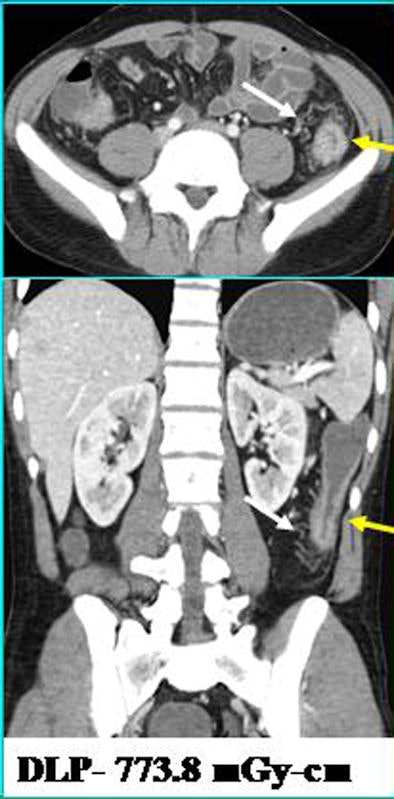

| FBP-enabled images acquired with a higher dose (above) are comparable to ASIR-enabled images (below). |